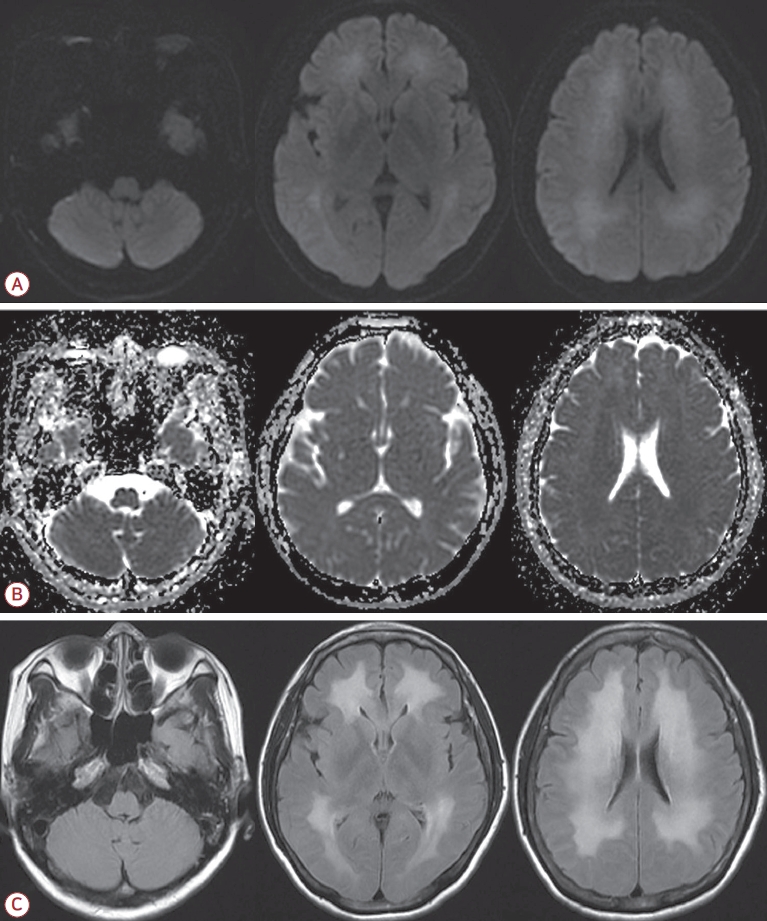

내원 당일 시행한 확산강조영상에서 양측 소뇌의 수평틈새 인근의 소뇌이랑에 대칭적인 고신호강도의 병변이 관찰되었다(Fig. 1-A). 이 병변은 겉보기확산계수지도영상에서는 저신호강도를 보였고(Fig. 1-B) 액체감쇠역전회복영상에서는 고신호강도를 보였다(Fig. 1-C). 그 외 다른 뇌 부위에서의 병변은 관찰되지 않았다(Fig. 1).

그러나 환자는 퇴원 2주 후부터 말수가 줄어들고 보행이 느려지며 종종걸음을 걷게 되었다. 또한 식사를 잘 하지 않으며 멍하게 있는 모습이 자주 관찰되었다. 이후로도 점차 악화되어 퇴원 3주째에는 자발적 행동이 거의 없어지고 누워 있으려고만 해서 다시 입원하였다. 신경계 진찰상 의식은 각성 상태였지만 말을 하지 않았고 질문에 대답하지 않았으며 명령 수행도 하지 않았다. 간이정신상태 검사(mini-mental state examination)도 시행하였으나 전혀 협조가 되지 않았고 대답도 하지 않아서 평가가 불가능하였다. 근력은 사지 모두 grade 3 정도로 양쪽 팔을 위로 올리는 것과 부축해서 서는 것은 가능하였으나 걷지는 못하였다. 손가락코 검사, 발꿈치정강이 검사, 일자보행 검사 등의 소뇌기능 검사는 협조가 되지 않아서 평가할 수 없었다. 통증 자극에 대한 반응이 양측에서 감소되어 있었고 사지에서 경축(rigidity)이 관찰되었다. 건반사는 사지에서 정상적이었고 바뱅스키징후는 관찰되지 않았다. 자기공명영상에서는 이전의 소뇌의 병변은 사라졌지만 새롭게 양측 피질하백질에 광범위한 고신호강도가 확산강조영상과 액체감쇠역전회복영상에서 관찰되었다(Fig. 2). 자기공명혈관조영 검사에서 뇌혈관의 이상 소견은 없었다.